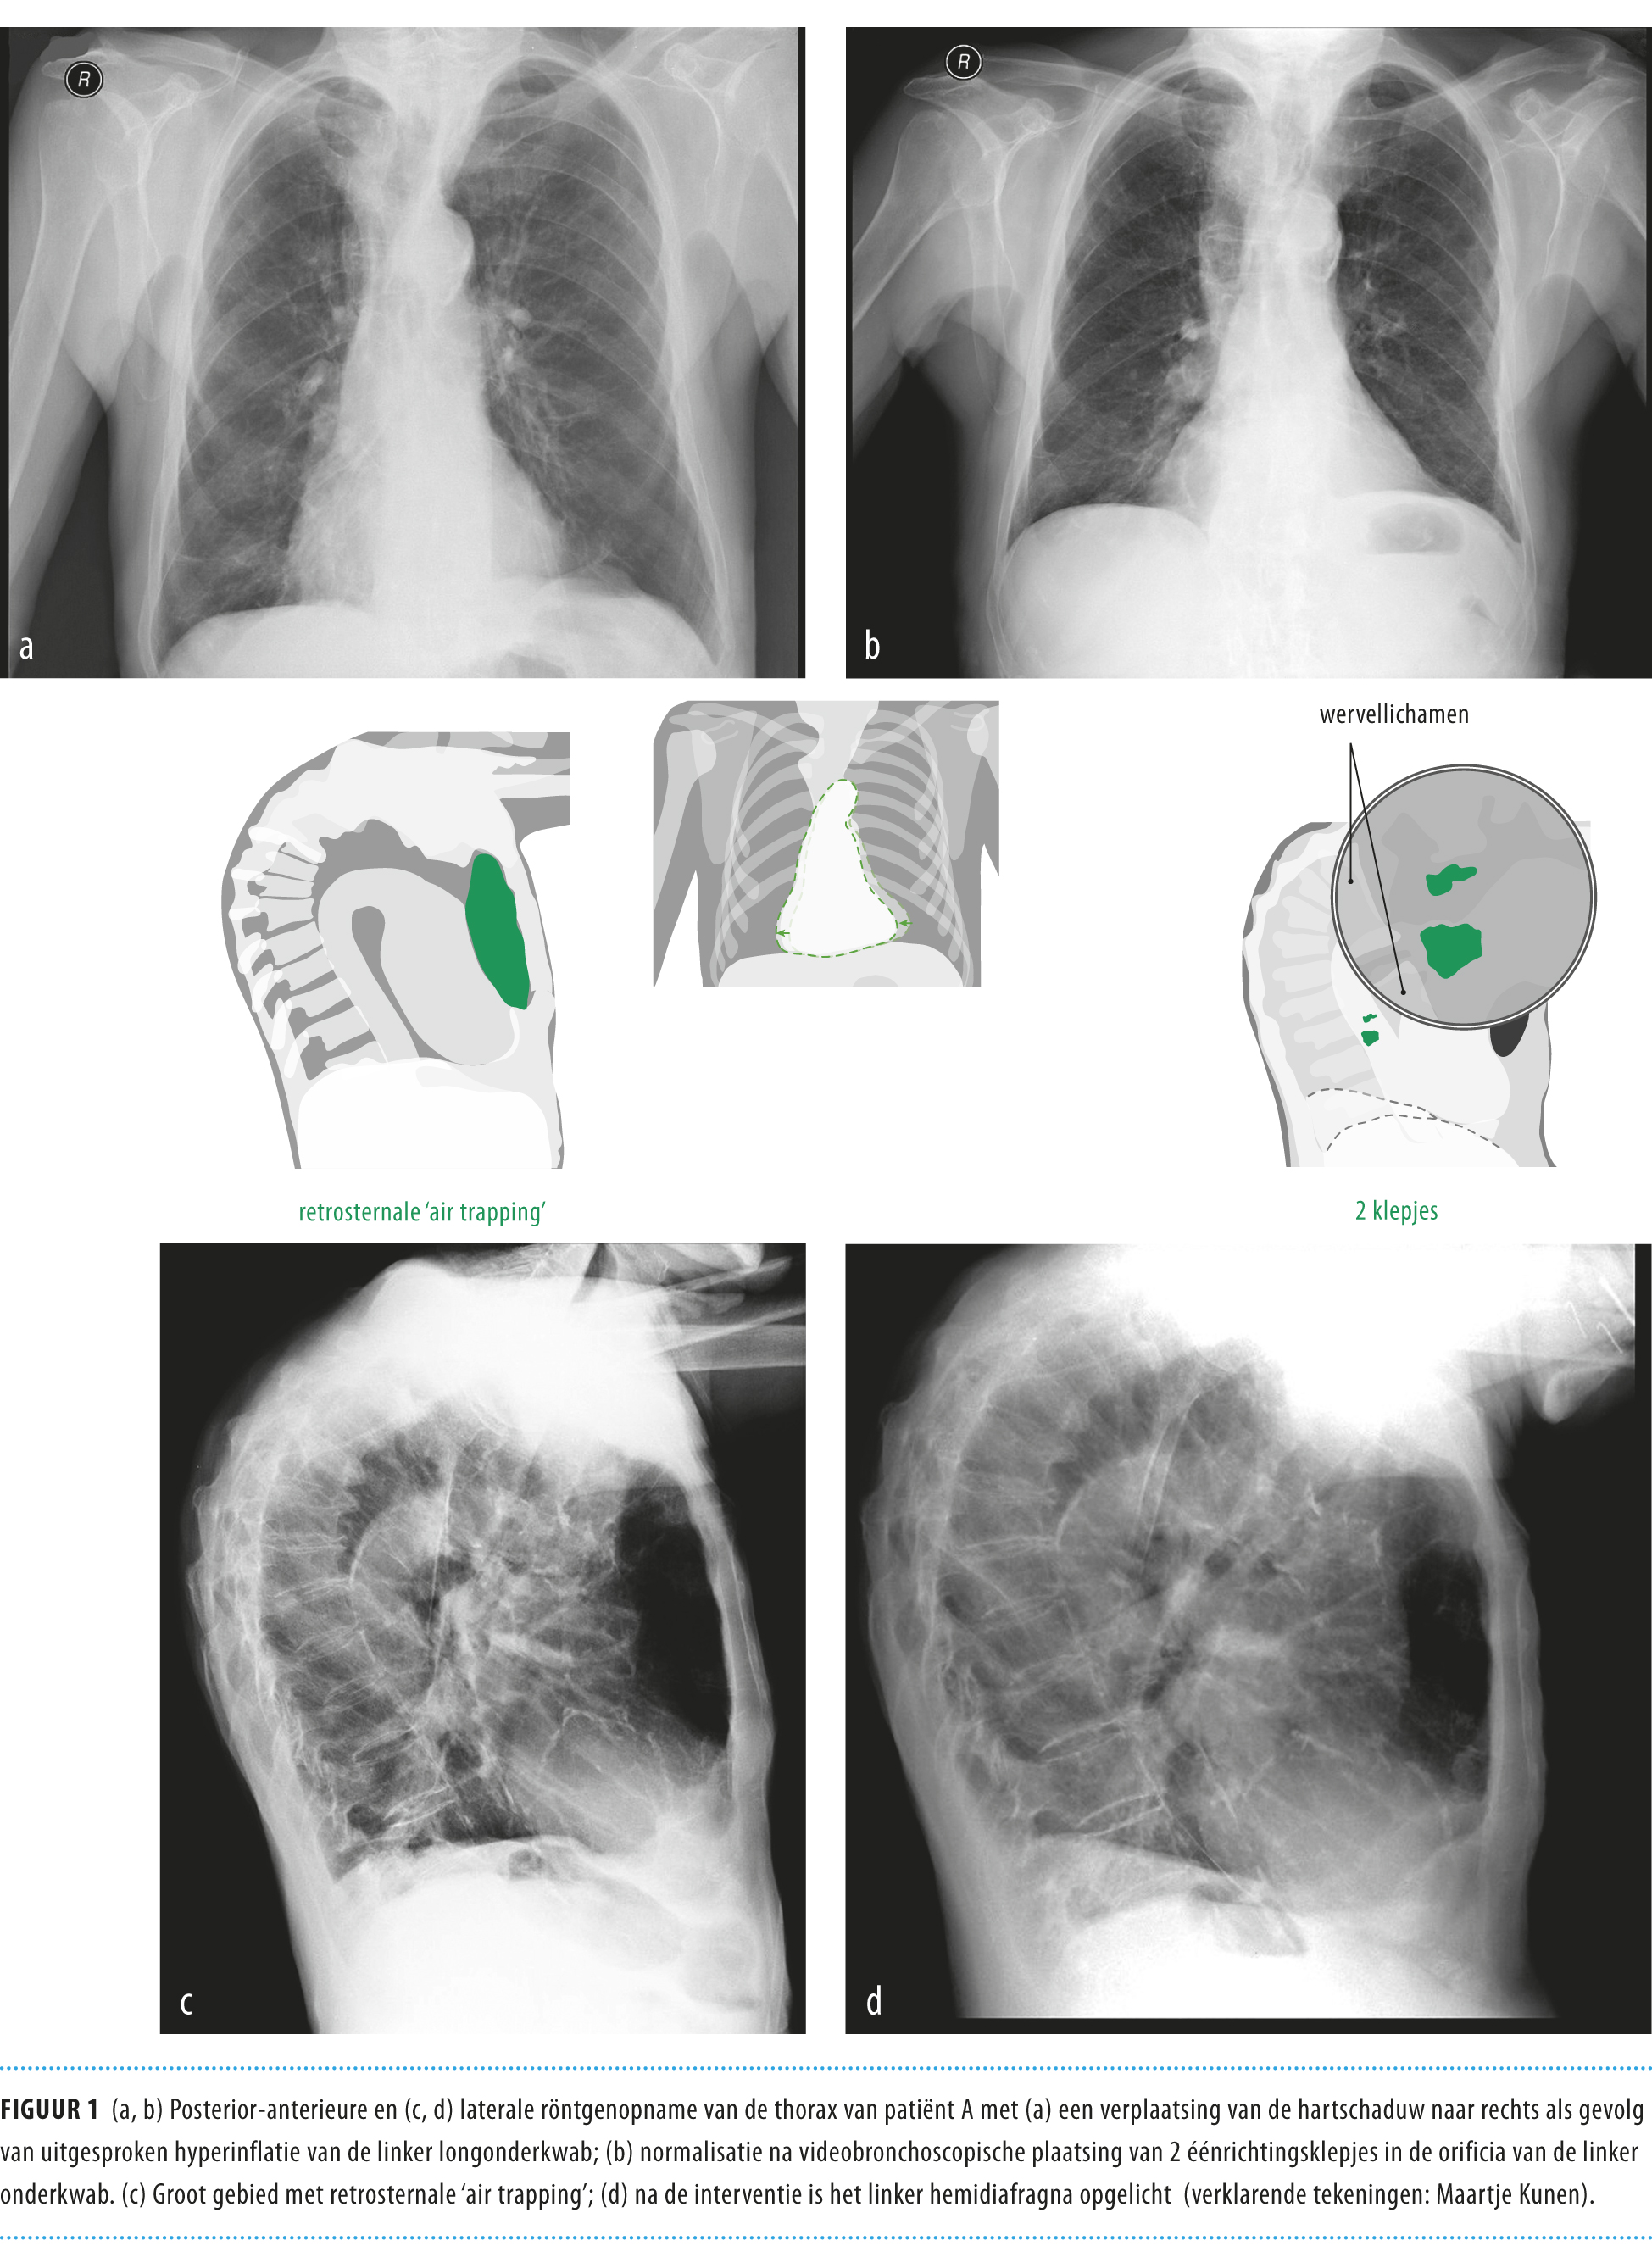

Ernstig Longemfyseem Bij Een 84-jarige Behandeld Door via www.ntvg.nl

Ernstig longemfyseem bij een 84-jarige behandeld door